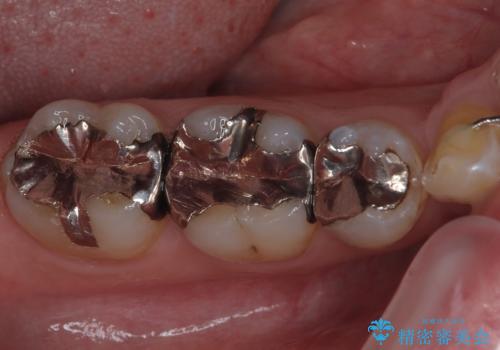

- 当院にて矯正治療を終えた患者様で銀歯を白くしたいとのことで来院された患者様です。神経の反応を確認し詰め物の範囲も大きいためフルジルコニアクラウンにて治療を行うことにしました。

拡大鏡視野下でメタルインレー、虫歯を除去しフルジルコニアクラウンに適した形に整えました。